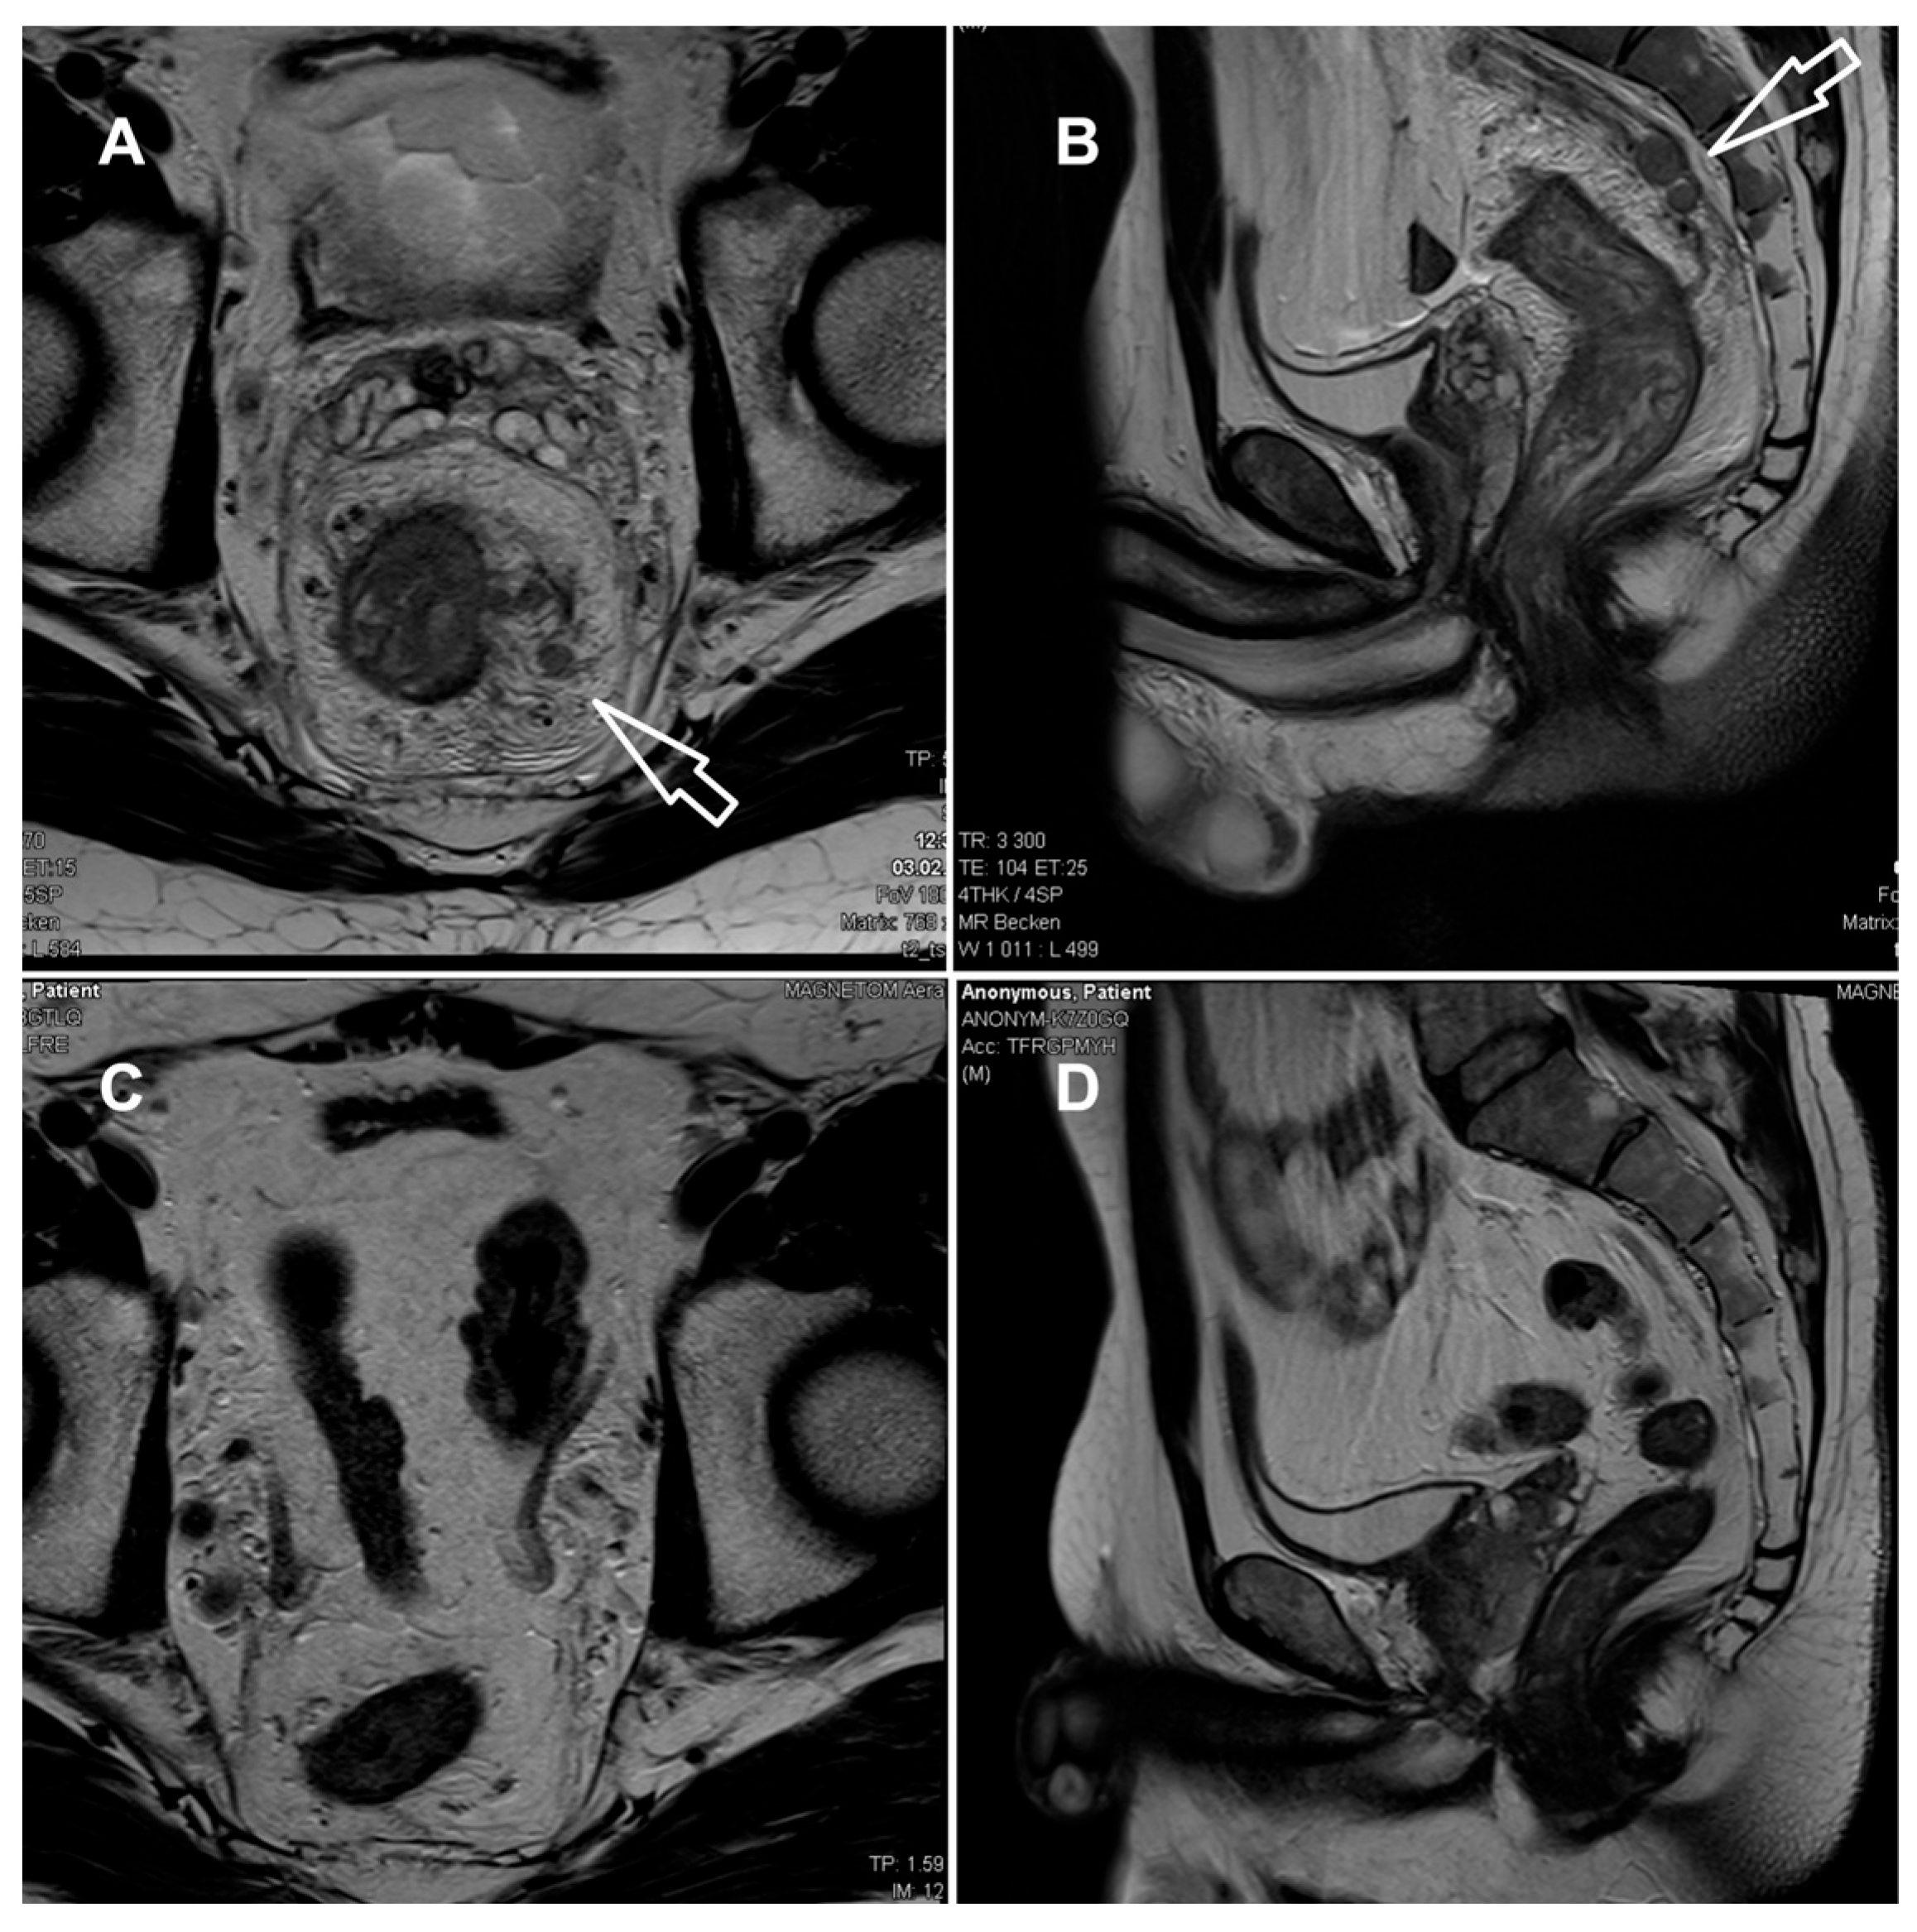

2. Case Presentation